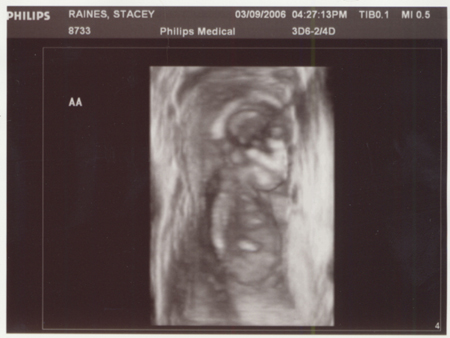

Yep, TWINS!! And if you think trying to tell the difference above now is difficult, just wait until July/August when you can hold them.

Nope, they are not identical, they are fraternal. So this can be a picture of two girls, two boys or one of each. So congrats to all you Grandma, Grandpa, Aunt, Uncle and cousins out there...